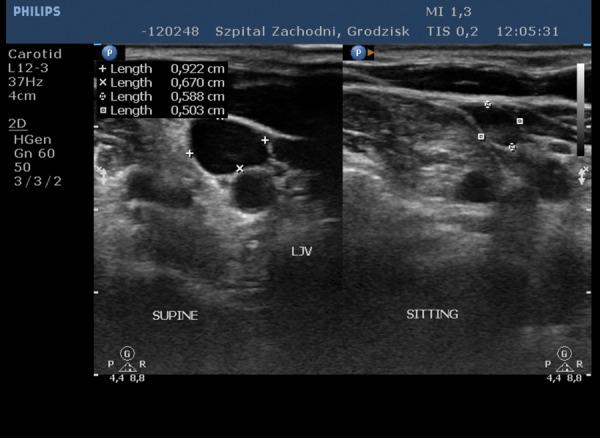

慢性脑脊髓静脉功能不全与多发性硬化症之间存在关联吗?——一项批判性综述。

Is there any relation between chronic cerebrospinal venous insufficiency and multiple sclerosis? - a critical review.

Summary Though the etiology of multiple sclerosis remains unknown, the widely accepted explanation is that it has an autoimmune inflammatory background. In 2006 Paolo Zamboni renewed the somewhat forgotten vascular theory of the pathogenesis of multiple sclerosis, proposing the new entity of 'chronic cerebrospinal venous insufficiency'. As a result of this hypothesis, Zamboni suggested an endovascular treatment for multiple sclerosis involving venoplasty of the internal jugular vein and the azygos vein. Unfortunately, several teams have tried to replicate Zamboni's results without success. In this review, we present a chronological description of the results of the studies conducted by Zamboni and the later attempts to replicate his work. The main conclusion is that, taking into account results that are currently available, we should remain cautious and routine use of this treatment in patients should not be advisable.

摘要 尽管多发性硬化症的病因尚不清楚,但被广泛接受的解释是它具有自身免疫性炎症背景。2006年,保罗·赞博尼重新提出了某种程度上被遗忘的多发性硬化症发病机制的血管理论,提出了“慢性脑脊髓静脉功能不全”这一新概念。基于这一假说,赞博尼建议对多发性硬化症采用血管内治疗,包括颈内静脉和奇静脉的血管成形术。不幸的是,几个研究团队试图重现赞博尼的结果,但均未成功。在本综述中,我们按时间顺序描述了赞博尼所开展研究的结果以及后来试图重现其研究成果的情况。主要结论是,考虑到目前可得的结果,我们应保持谨慎,不建议在患者中常规使用这种治疗方法。